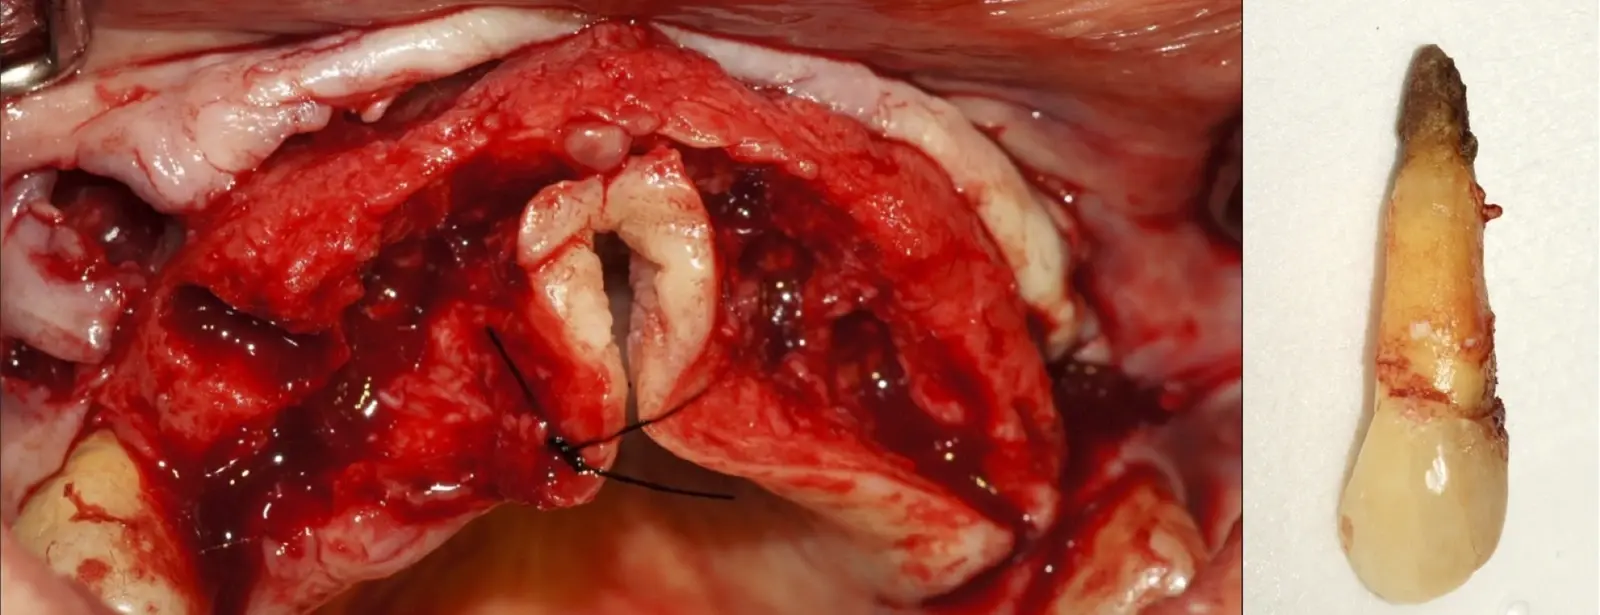

El procedimiento se inicia colocando anestesia y elevando un colgajo mucoperióstico a espesor completo y exponiendo la zona. En seguida se realiza la enucleación de la lesión, eliminando o creando una ventana en la lámina cortical que contiene el área del ápice.

El procedimiento se inicia colocando anestesia y elevando un colgajo mucoperióstico a espesor completo3 (incisión semilunar o intrasurcular con/sin protección papilar) y exponiendo la zona. En seguida se realiza la enucleación de la lesión, eliminando16 o creando una ventana17 en la lámina cortical que contiene el área del ápice; este retiro óseo se realiza con los insertos de forma aplanada dentada o inserto con cobertura diamantada plano o redondo, recordando ser lo más conservador posible (Figura 5).

Después de realizado el acceso e identificado el ápice, se procede a la limpieza de la zona con instrumentos manuales y/o con insertos diamantados de parte activa angulada para poder eliminar todo el tejido patológico del perímetro radicular apical y del tejido óseo circundante (Figura 6).

Una vez limpia la zona apical, se corrobora la integridad de la raíz y se evalúa el grado de extensión de la lesión. Si el defecto óseo es pequeño, se procede a realizar la preparación del conducto y obturación retrógrada de ser el caso. Si el defecto óseo es de gran tamaño e inaccesible a los insertos, se procede a realizar un corte de por lo menos 3 mm de ápice radicular conteniendo los posibles conductos aún infectados11 empleando habitualmente insertos de borde aserrado con/sin marcas de medición para un trabajo seguro7 (Figura 7).